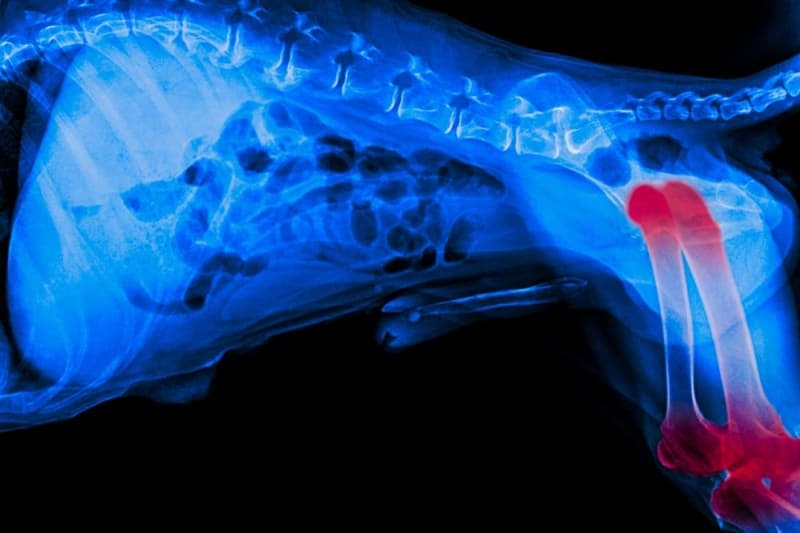

Joint Pain in Dogs

Our Norristown vets often see dogs in their office due to symptoms of joint pain. Although a common reason for joint pain is aging, there are effective treatments available to relieve discomfort in dogs of any age or activity level.

Dogs of all breeds and ages can experience joint pain, although it is more commonly observed in senior large breed dogs.